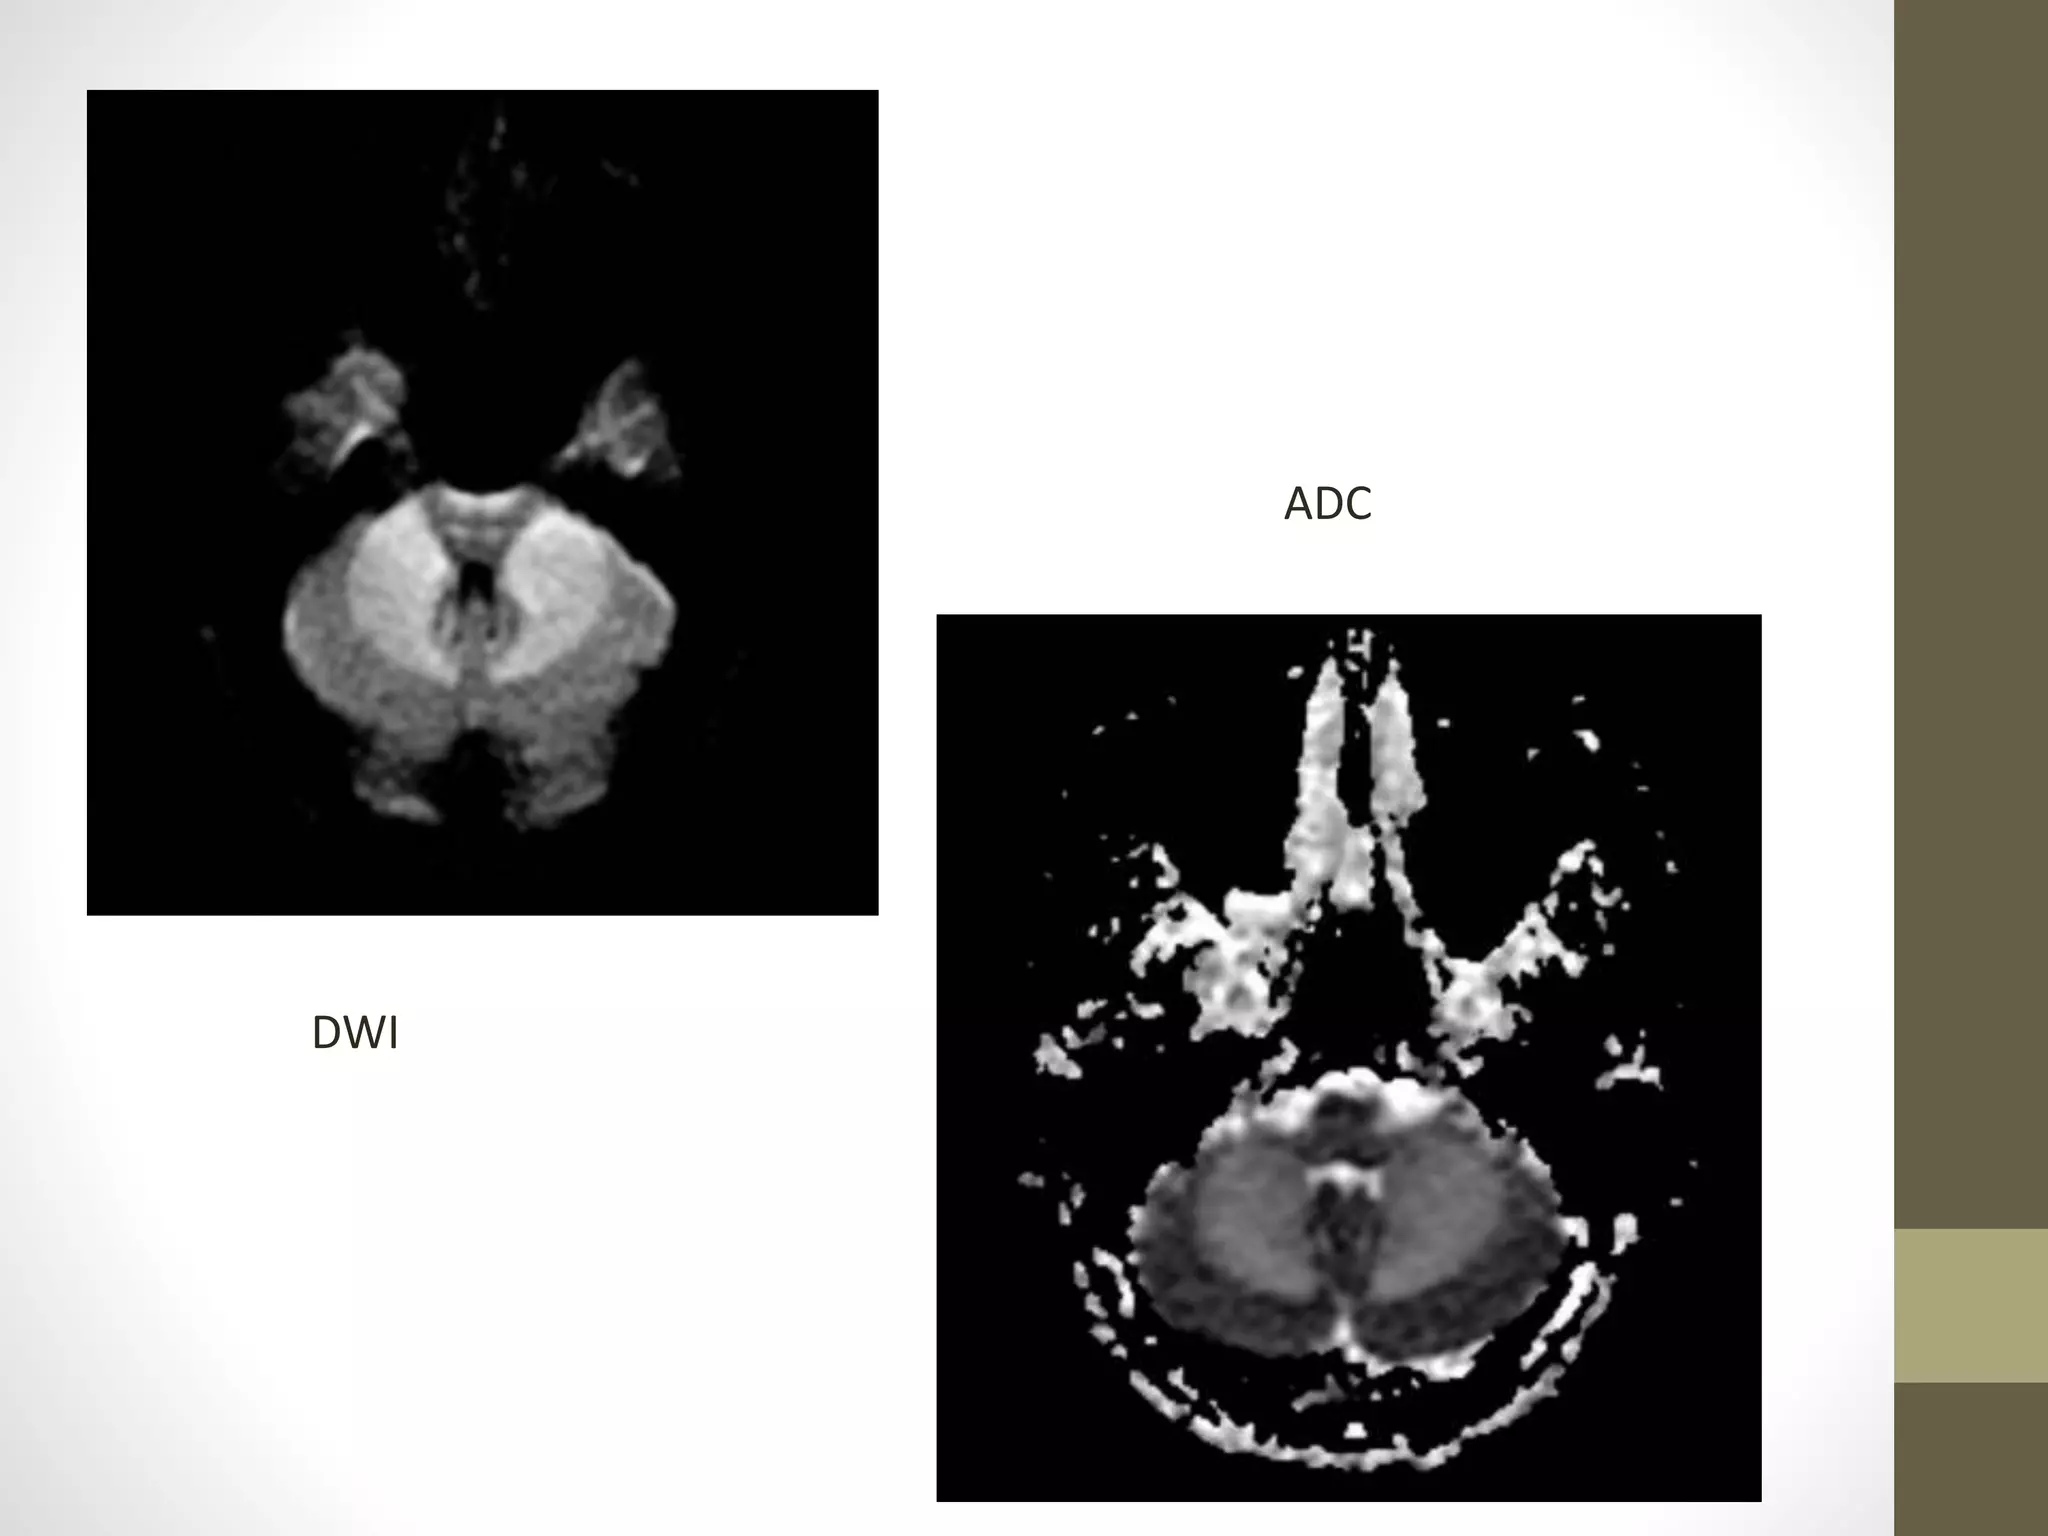

DWI

ADC

Apparent Diffusion Coefficient(contd) Differentiate T2 shine through effects or artifacts from real ischemic lesions. T 2 shine through • Signal intensity on DWI – not only on ADC but also on tissue T2. this can cause paradoxical decrease in signals of restricted diffusion or when diffusion is normal, can be mistaken for diffusion restriction.